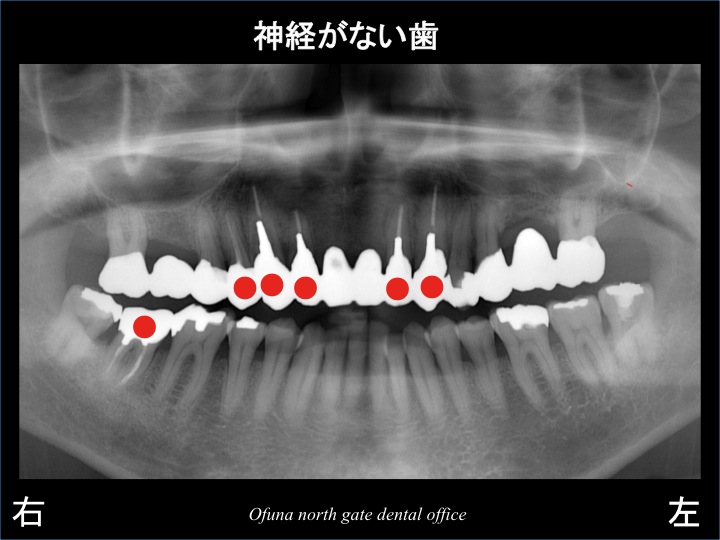

以下の●印は、神経がない歯です。

抜歯後に4歯欠損となった部位にインプラントを埋入した場合、

その周囲の歯が神経がないため、どのような治療設計にした方が良いのかは いつも悩みます。